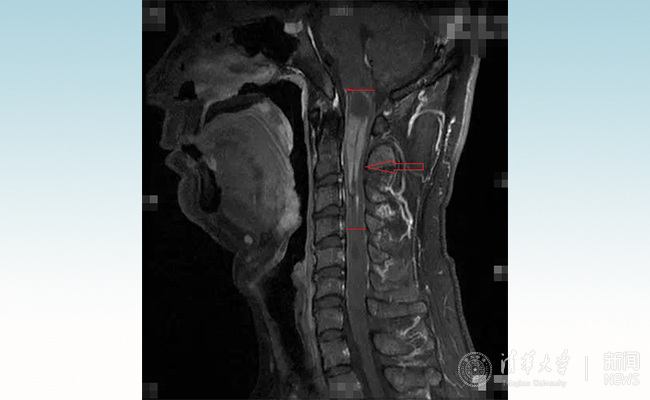

患者小智术前的核磁影像。

小智来自东北,靠开出租车维持一家生活。今夏,他开始出现双手麻木、胸部束缚感,经确诊系脊髓髓内肿瘤。他和妻子辗转国内多家医院,均因肿瘤位置靠近脑干禁区,且肿瘤很长而被拒收,12月,当小智来到北京清华长庚医院神经外科找到王贵怀教授时,他的手已经无法握住一双筷子。

从人体的后脑到颈部一直向下延伸到尾椎,是一根长长的管道,里面是一根手指粗细的脊髓,它就像一根“电缆”,里面布满了导线一样的神经,大脑通过这根“电缆”下达指令,并接收来自身体各个部位的信号。而延颈髓肿瘤,上端濒临脑干禁区,下端延伸几公分甚至几十公分,挤压正常的脊髓,导致神经传导出现了严重问题,患者因此出现无力、莫名的疼痛甚至瘫痪的症状。“延髓是生命中枢,相当于总闸,牵一发动全身。”王贵怀说。